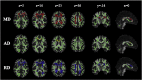

Diffusion MRI is used widely to probe microstructural alterations in neurological and psychiatric disease. However, ageing and neurodegeneration are also associated with atrophy, which leads to artefacts through partial volume effects due to cerebrospinal-fluid contamination (CSFC). The aim of this study was to explore the influence of CSFC on apparent microstructural changes in mild cognitive impairment (MCI) at several spatial levels: individually reconstructed tracts; at the level of a whole white matter skeleton (tract-based spatial statistics); and histograms derived from all white matter. 25 individuals with MCI and 20 matched controls underwent diffusion MRI. We corrected for CSFC using a post-acquisition voxel-by-voxel approach of free-water elimination. Tracts varied in their susceptibility to CSFC. The apparent pattern of tract involvement in disease shifted when correction was applied. Both spurious group differences, driven by CSFC, and masking of true differences were observed. Tract-based spatial statistics were found to be robust across much of the skeleton but with some localised CSFC effects. Diffusivity measures were affected disproportionately in MCI, and group differences in fornix microstructure were exaggerated. Group differences in white matter histogram measures were also partly driven by CSFC. For diffusivity measures, up to two thirds of observed group differences were due to CSFC. Our results demonstrate that CSFC has an impact on quantitative differences between MCI and controls. Furthermore, it affects the apparent spatial pattern of white matter involvement. Free-water elimination provides a step towards disentangling intrinsic and volumetric alterations in individuals prone to atrophy.